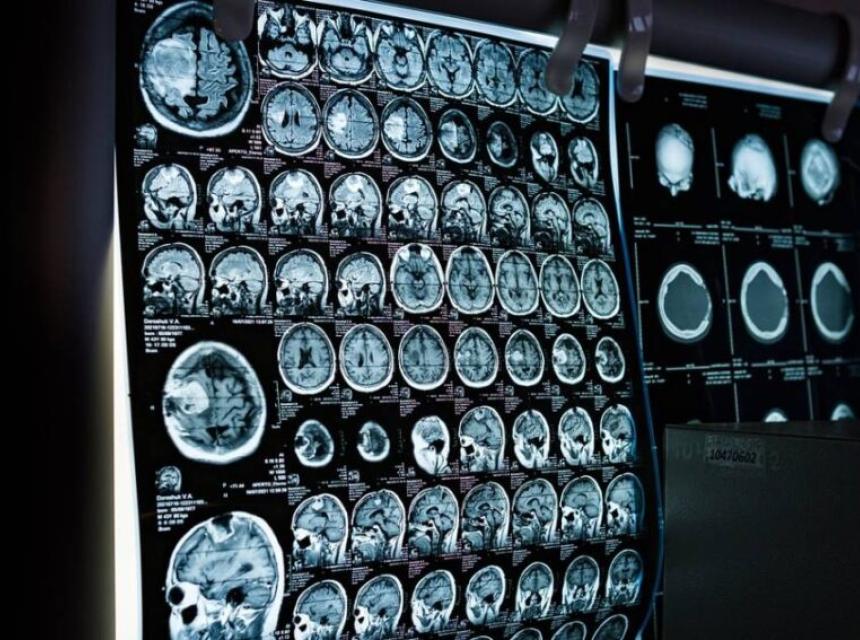

U studiji, objavljenoj u medicinskom časopisu koji izdaje Američko medicinsko udruženje koja je ranije predstavljena na Međunarodnoj konferenciji udruženja za Alzheimer u Amsterdamu, navodi se da je nakon 76 sedmica liječenja “donanemab” uspio usporiti opadanje sposobnosti za 35,1 dosto kod ljudi s ranim Alzheimerom čiji su skenovi mozga pokazali niske ili srednje nivoe proteina tau.